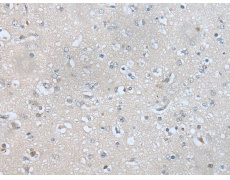

IHC positive control:

Human brain

IHC Recommend dilution:

25-100